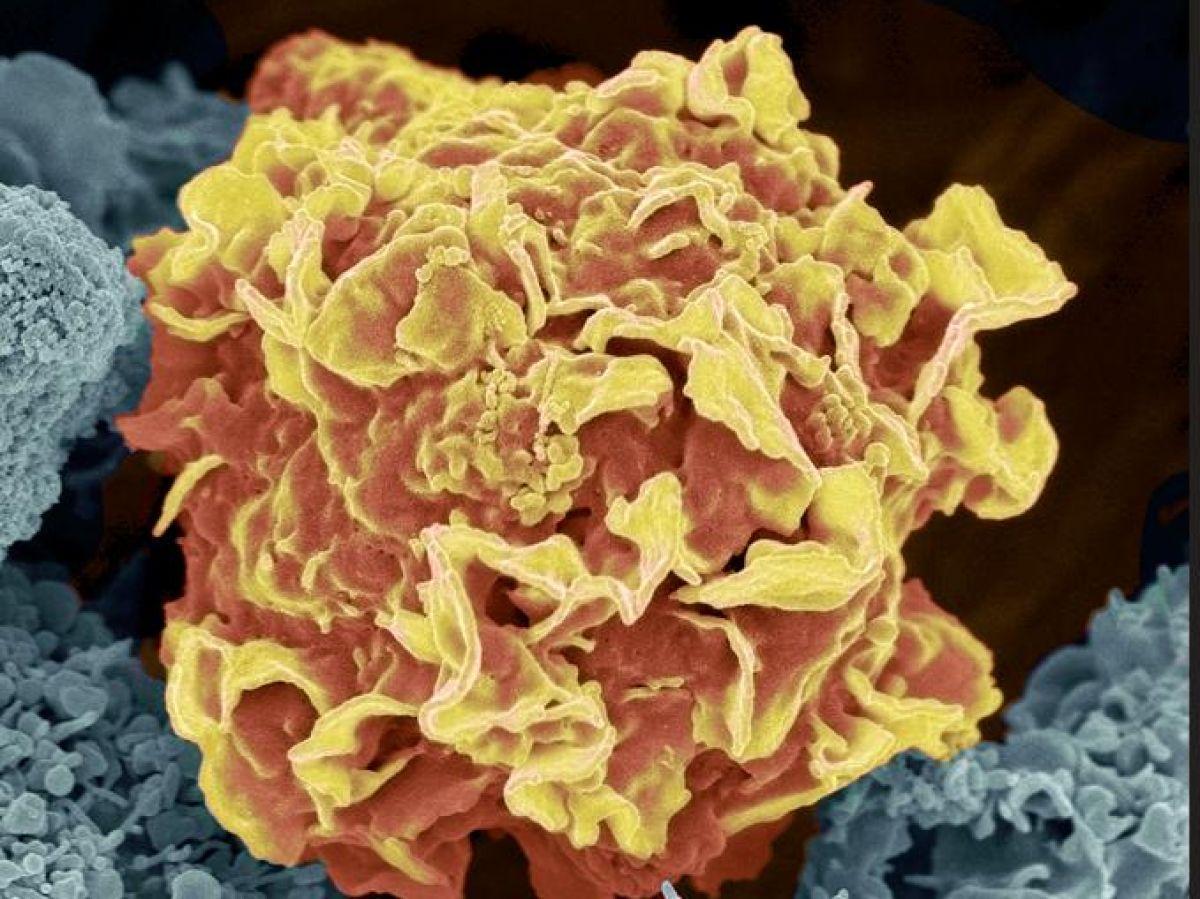

Une approche qui a transformé la vision du cancer: une tumeur n’est pas un bloc homogène. Elle est composée d’une multitude de cellules différentes: certaines prolifèrent rapidement, d’autres résistent aux traitements, d’autres encore parviennent à échapper au système immunitaire… Le séquençage de l’ARN en cellule unique permet de mesurer, pour chaque cellule, quels gènes sont activés ou éteints à un instant donné. Résultat: des jeux de données gigantesques, parfois constitués de millions de cellules décrites par plusieurs milliers de variables. C’est là que les IA génératives, en tant que grands modèles de langage, changent la donne.

En IA, le nerf de la guerre reste la qualité, la diversité et la quantité des données. S’il existe déjà des modèles capables de prédire une réponse à partir de données d’entrée, aucun n’a pu bénéficier d’une validation clinique. « La difficulté principale c’est l’hétérogénéité intratumorale, reprend le chercheur. Une tumeur est composée de clones différents, qui n’évoluent pas de la même façon. Les modèles single cell sont prometteurs, mais l’accès à ces données reste coûteux. » Même si le fait de pouvoir « leur parler » directement a rebattu les cartes.

L’IA est également de plus en plus utilisée pour analyser des images de tissus prélevés lors de biopsies ou d’opérations chirurgicales. Ces images, observées habituellement au microscope par des médecins spécialistes, peuvent aujourd’hui être examinées par des algorithmes capables de repérer des cellules cancéreuses, d’évaluer le degré d’agressivité d’une tumeur ou d’identifier des indices utiles pour le pronostic. Ces applications partagent plusieurs caractéristiques: elles reposent sur des tâches bien définies, sur des données standardisées et sur des performances mesurables. Fondées sur la vision par ordinateur, elles ont émergé il y a maintenant près de dix ans et ont fait l’objet d’essais cliniques, d’évaluations réglementaires et, pour certaines, sont déjà intégrées aux flux de soins hospitaliers.